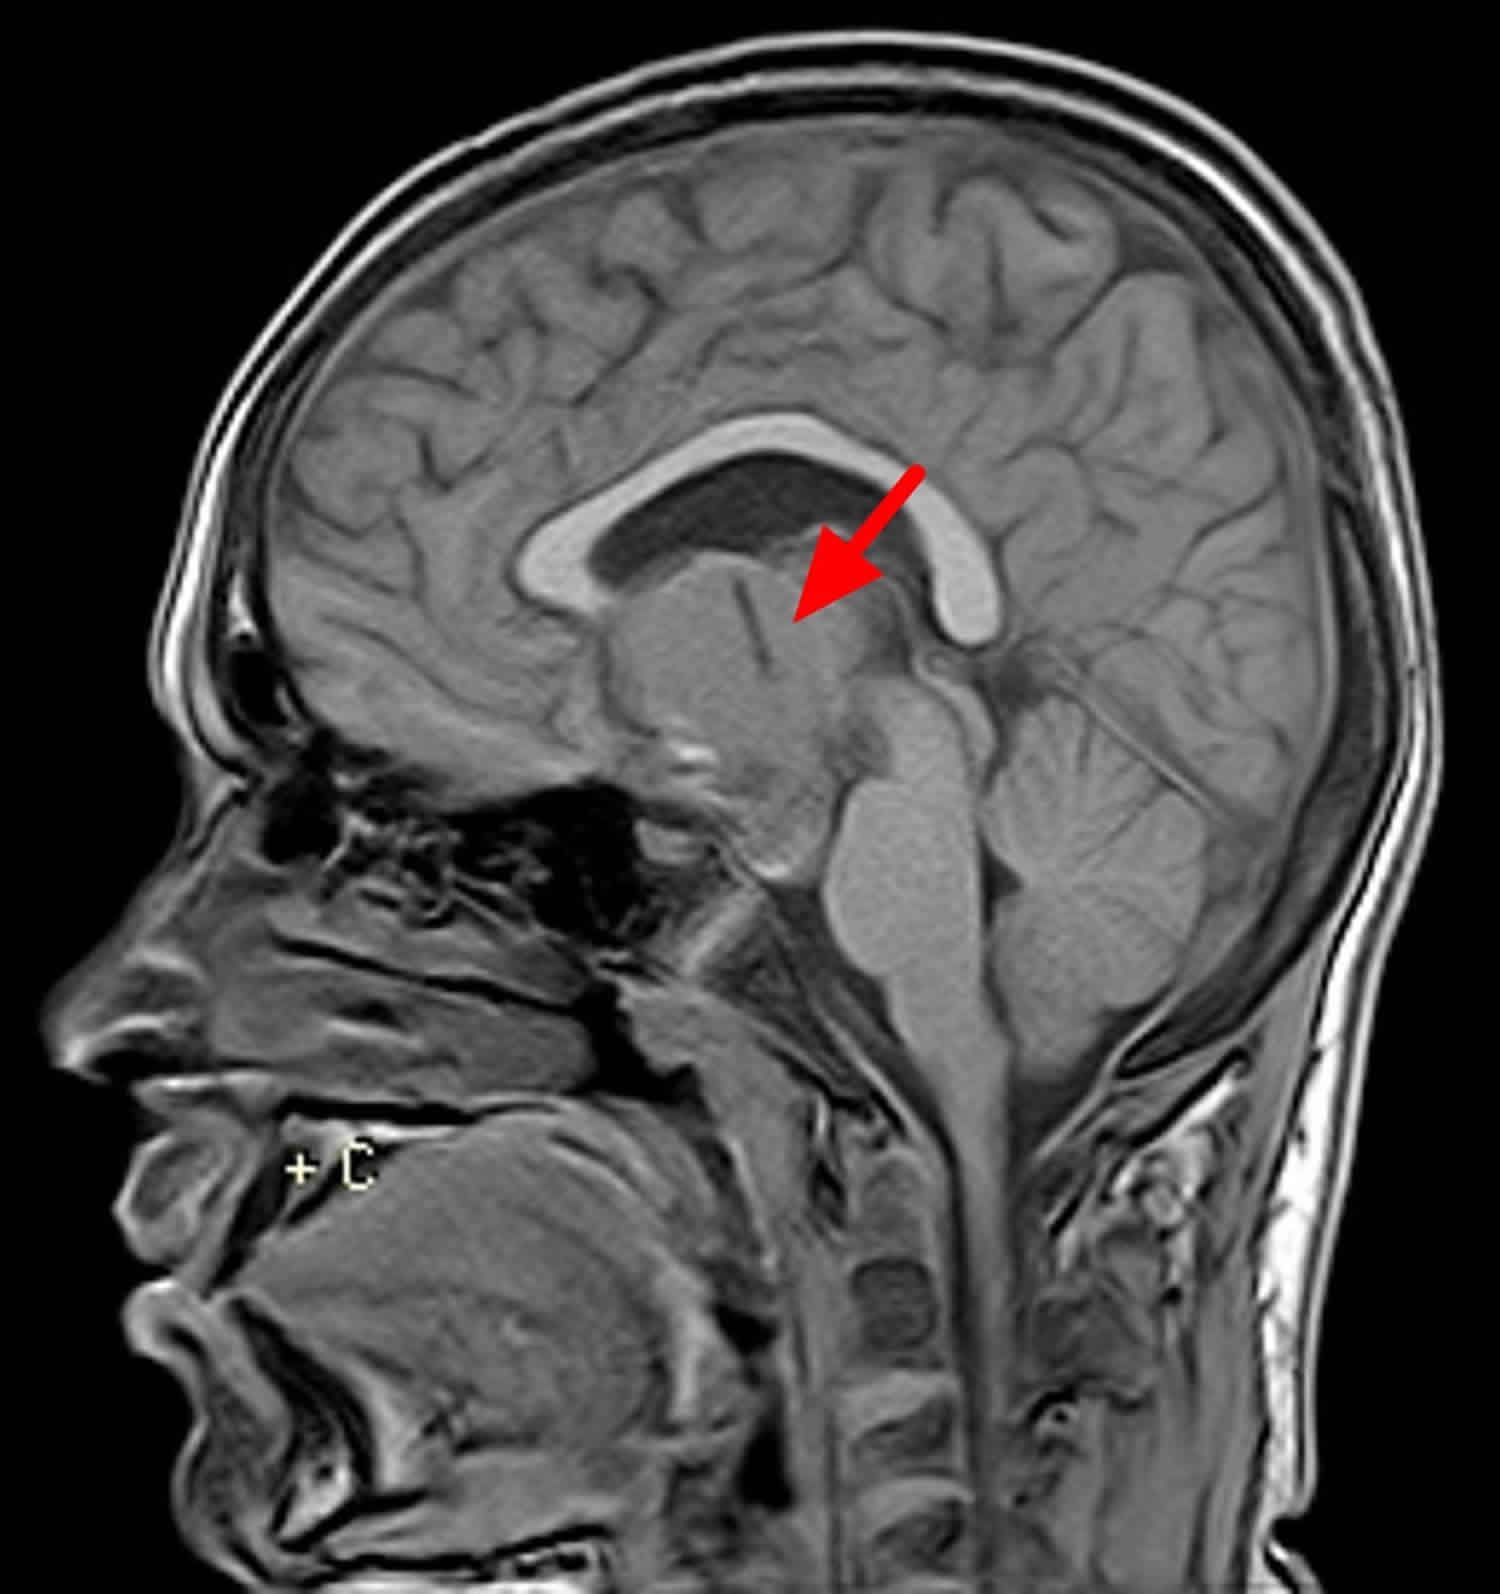

Craniopharyngiomas are the benign tumors of suprasellar region arising from embryologic remnants of Rathke's pouch and comprise 20-25% of all pituitary mass lesions. They result in visual field defects (bitemporal hemianopia) due to compression of optic chiasm and may also cause headaches, papilledema, and changes in mentation. They may even cause hyperprolactinemia, diabetes insipidus, and panhypopituitarism. They are diagnosed on MRI and their treatment is surgical excision (total or partial resection) with or without radiation therapy.